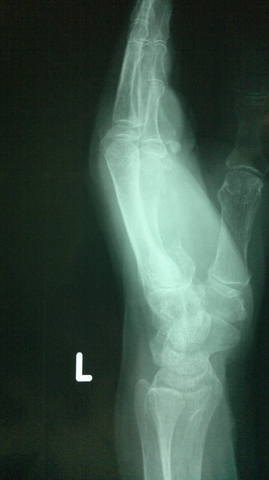

Метастаз во 2-ю пястную кость левой кисти

<br /><br />Женщина, 60 лет. Плазмоцитома.<br /><br />Опухолевый узел в области кисти болел и увеличивался в размерах с течением времени не смотря на проводимое лечение.<br /><br />

<br /><br />Выполнена ампутация 2 луча левой кисти в пределах здоровых тканей.